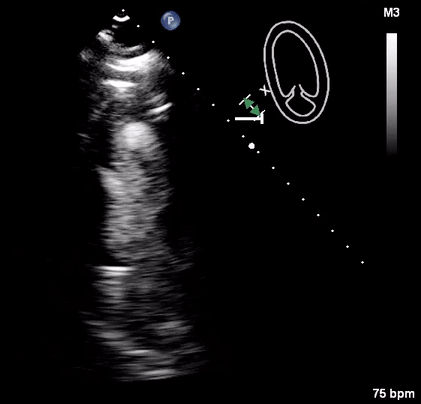

Physical, mental, and emotional stressors have been well known to adversely affect cardiac function. A rare complication of such stressors is stress cardiomyopathy, otherwise known as takotsubo cardiomyopathy. First identified in Japan in the 1990s, takotsubo cardiomyopathy classically presents with systolic dysfunction and apical ballooning. In this report, we present the case of a patient with a medical history of alcohol abuse who presented to the emergency department after being found unresponsive by her family. Transthoracic echocardiography revealed takotsubo cardiomyopathy, which was likely secondary to alcohol withdrawal. Alcohol withdrawal causes an imbalance between various neurotransmitters such as GABA and glutamate. This imbalance caused autonomic overactivity, which manifested as stress cardiomyopathy.